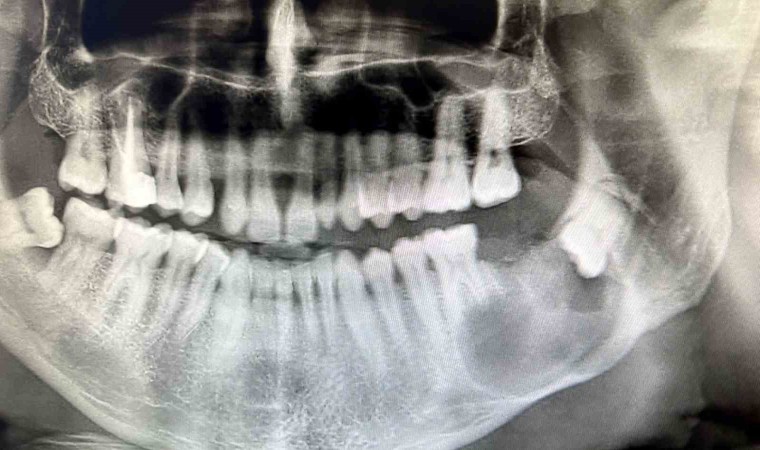

Sivas Ağız ve Diş Hastalıkları Hastanesinde benzerine az rastlanan bir ameliyat gerçekleştirildi. Çenesinde ileri derecede apse şikayetiyle hastaneye başvuran 43 yaşındaki hasta, uygulanan yöntemle sağlığına kavuştu. 37 numaralı dişi çekilen hastanın tomografi görüntüleri alındı. Hastanın 3D yazıcı sistemi ile çene modeli oluşturuldu. Oluşturulan 3D çene modeli üzerinde titanyum plak uyarlaması yapıldı. Uyarlamanın ardından Ağız, Diş ve Çene Cerrahisi Uzmanı Yunus Balel, genel anestezi altında hastayı ameliyat ederek, titanyum plak işlemini hastaya uyguladı.

Türkiye’de bu uygulamanın çok sık yapılmadığını ifade eden Ağız, Diş ve Çene Cerrahisi Uzmanı Yunus Balel, “Hastamız, sol alt çenede apse şikayeti ile başvurdu. Yaptığımız inceleme sonucu gömülü 20 yaş dişin etrafında büyük bir kist olduğunu tespit ettik. Hastayı genel anestezi altında opere etmeye karar verdik. Kisti temizledikten sonra çene çok zayıf kaldı. Hastanın çenesinin kırılmaması için büyük bir plak takmak zorunda kaldık” dedi.

“Bu uygulama, Sivas gibi genel anestezi ünitesi olan hastanelerde nadir yapılan işlemlerdendir. Bu kistler sınırsız büyüme potansiyeline sahiptir. Biz hastamızı geç evrede yakalamışız. 3D modelleme fikri benim aklıma geldi. Kullandığımız plak titanyum malzeme. Bu plağın bükümü ameliyat esnasında çok zor. Yaklaşık yarım saat süren bir durum. Bu da hastanın fazla süre entübe olmasına neden oluyor. 3 boyutlu bir model ürettik. Ağız dışında plağı uyumladık, ameliyat esnasında da 5 dakika uğraşarak uyumlamalara devam ettik. Bu model işimizi yarım saat ile 1 saat arası kolaylaştırdı.”